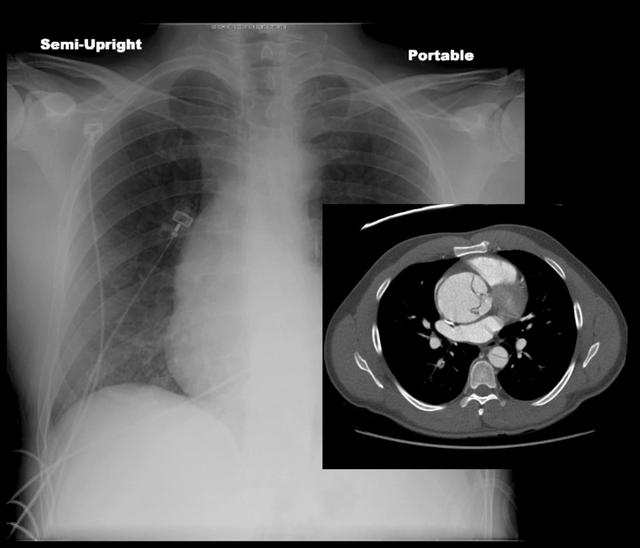

In this video course, Dr. Mohamed Muftah will explain three common deadly diseases that can be diagnosed from CT scans of the chest and present with chest pain.

- Learn CT scan findings of aortic dissection.

-Learn how to diagnose submassive and massive pulmonary embolism.